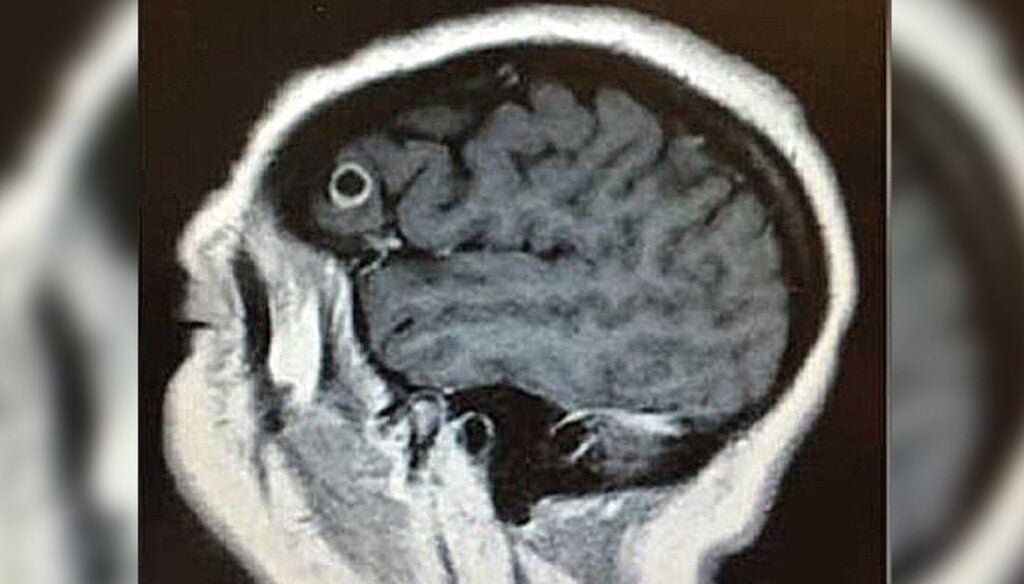

Pocas veces en la vida te alegras de que los médicos te digan que tienes una tenia en el cuerpo desde hace un año. El caso médico de Rachel Palma es una de esas ocasiones. Cuando le dijeron que tenía un gusano encerrado en su cerebro Palma no podía estar más feliz. La mujer, neoyorquina…